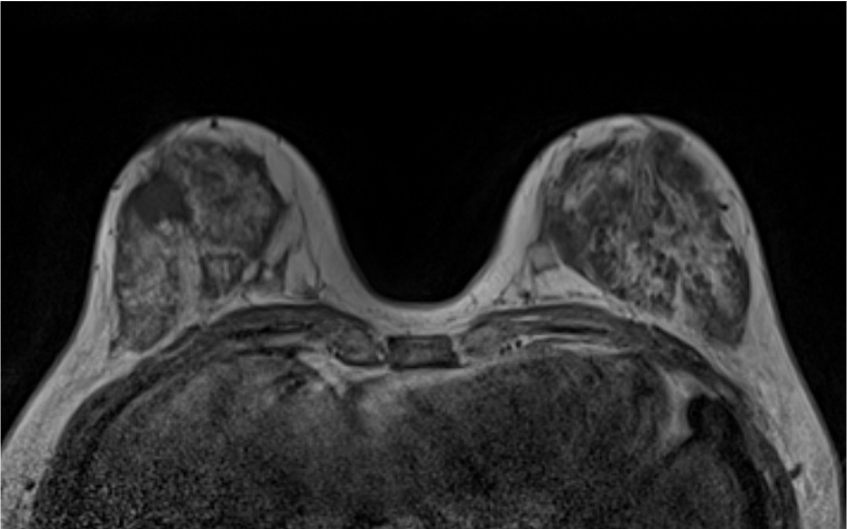

2. T2強調画像 (造影前)

乳癌の病変は、背景乳腺より軽度高信号の腫瘤を示している。明らかな腫瘍内壊死や周囲の浮腫は認めない

3. T1強調画像 (造影前)

乳癌の病変は、辺縁不整な腫瘤(Mass)を示している。